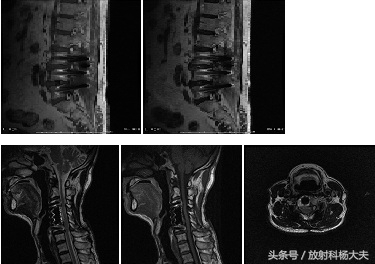

其实除了假牙,在磁共振的检查中,还有很多!如最常见的腰椎或者颈椎椎间盘手术,应用钛合金材料进行支撑或固定。由于其材质较好,图像伪影基本不影响诊断。(前提是得明确的知道这些植入物是能进磁场的,这很重要!)

从上图中可以发现,在颈椎及腰椎的固定术中,其所用材质较好,相对于假牙的不同材质,其对材质的要求比较严格,所产生的伪影较小,能够满足临床的诊断与鉴别诊断。